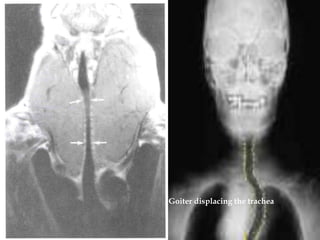

Nodular goiter

Goiter displacing the trachea

Nodular goiter Goiter displacing the trachea